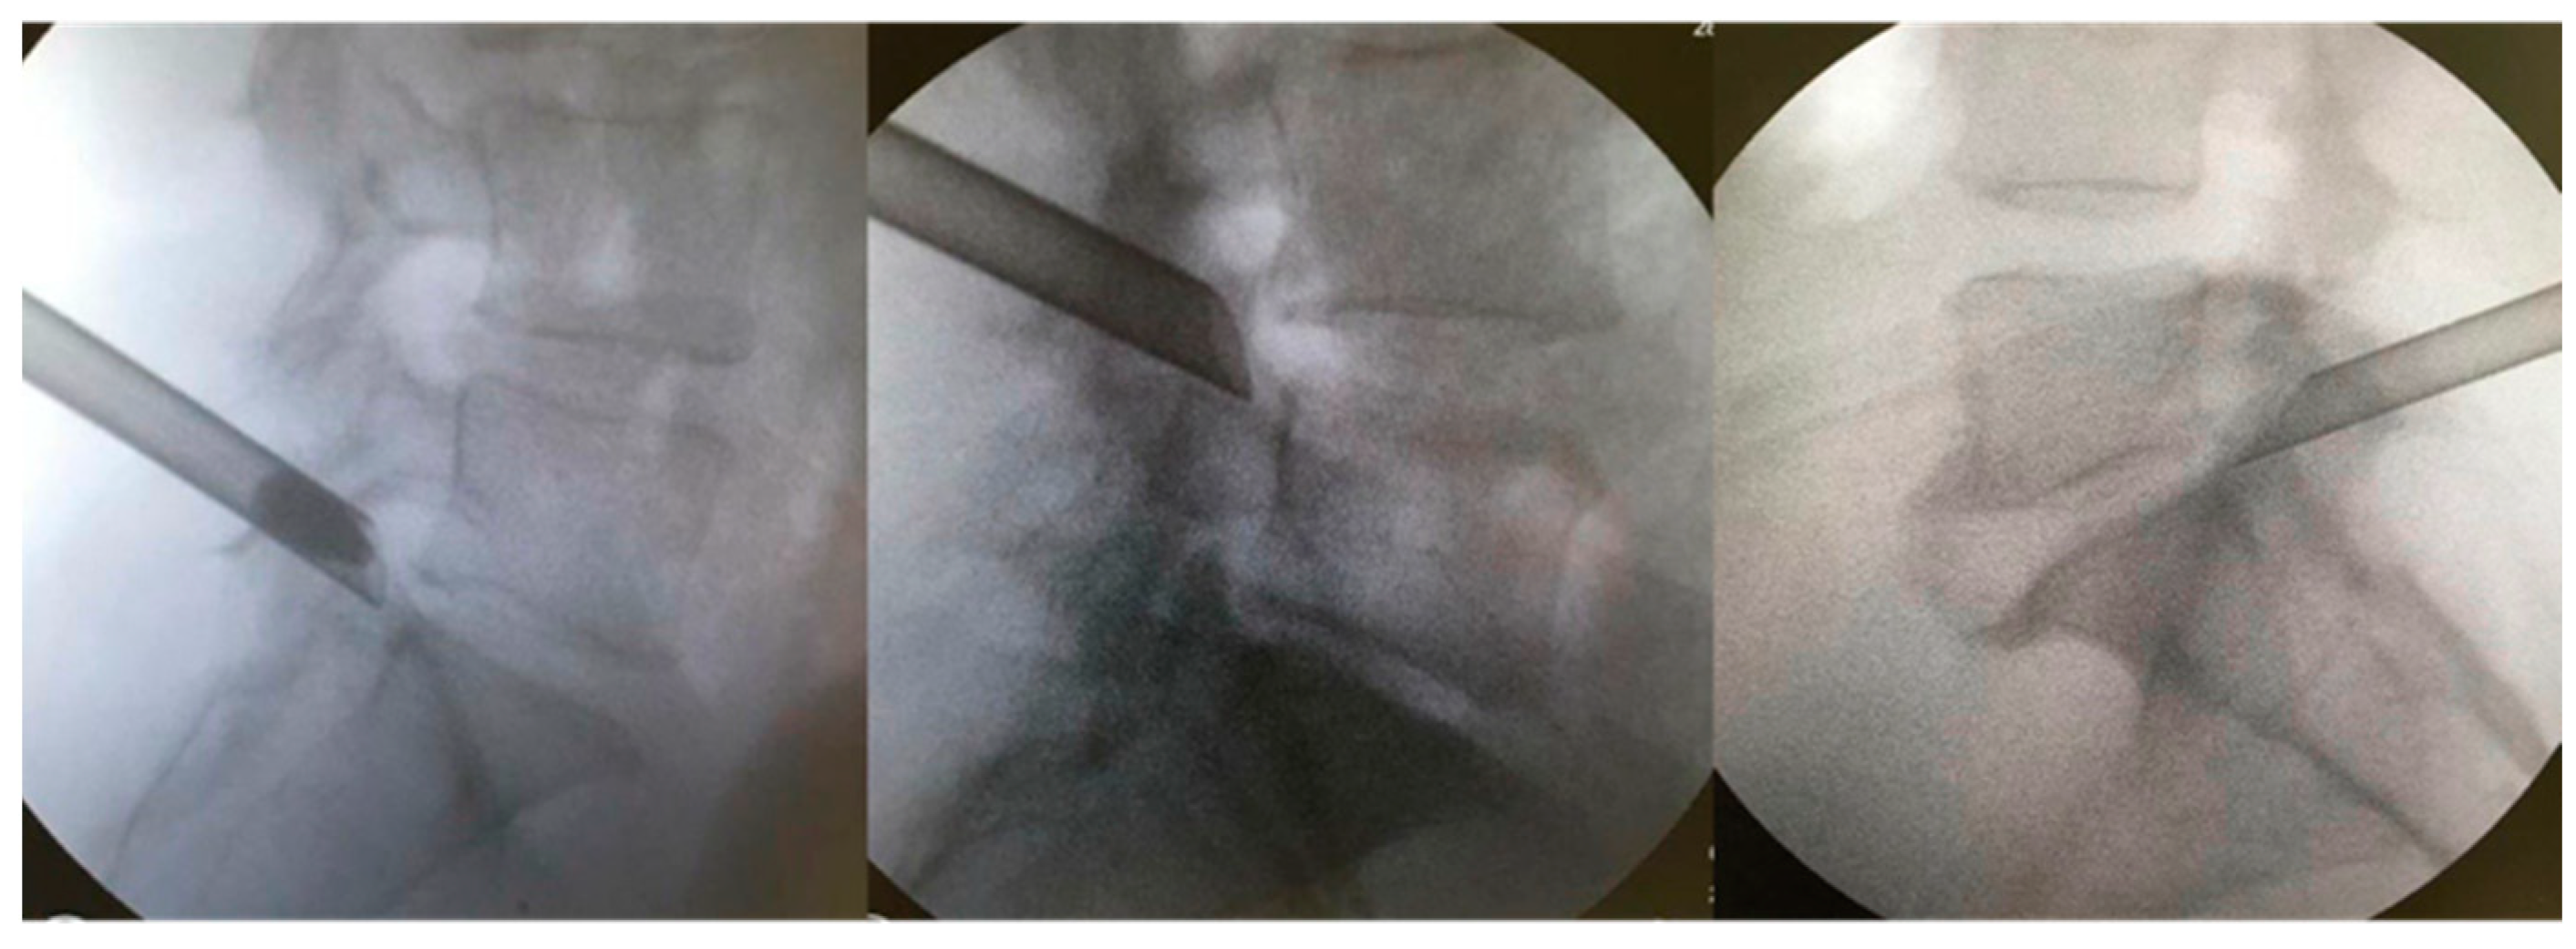

Figure 1.

Different reference points in the posterolateral approaches [7,10,11,12,13,16].